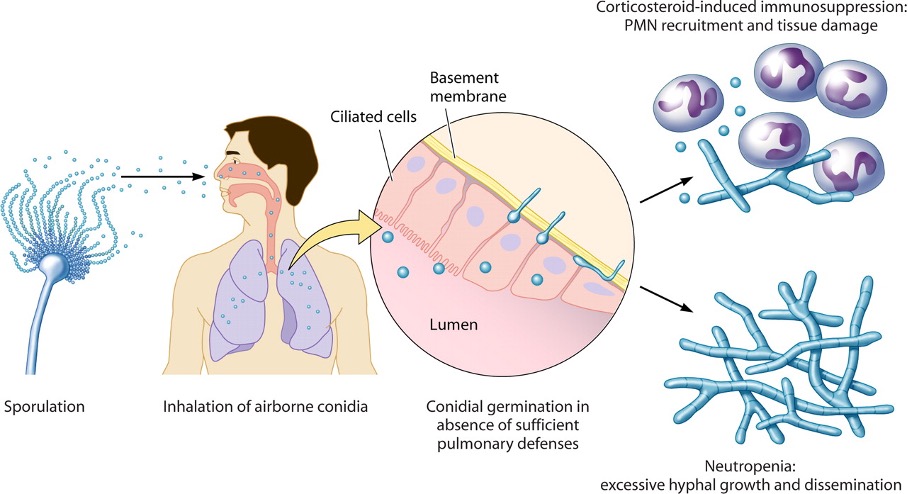

Infectieuze levenscyclus van A. fumigatus. Aspergillus is alomtegenwoordig in het milieu en ongeslachtelijke voortplanting leidt tot de productie van conidia in de lucht. Inhalatie door specifieke groepen patiënten met immunosuppressie resulteert in de vestiging van conidium in de longen, kieming en PMN-gemedieerde schimmelcontrole met significante ontsteking (therapie met corticosteroïden) of ongecontroleerde hyfengroei met een gebrek aan PMN-infiltraten en, in ernstige gevallen, verspreiding (neutropenie).

Bron: T. Dagenais et al, 2009